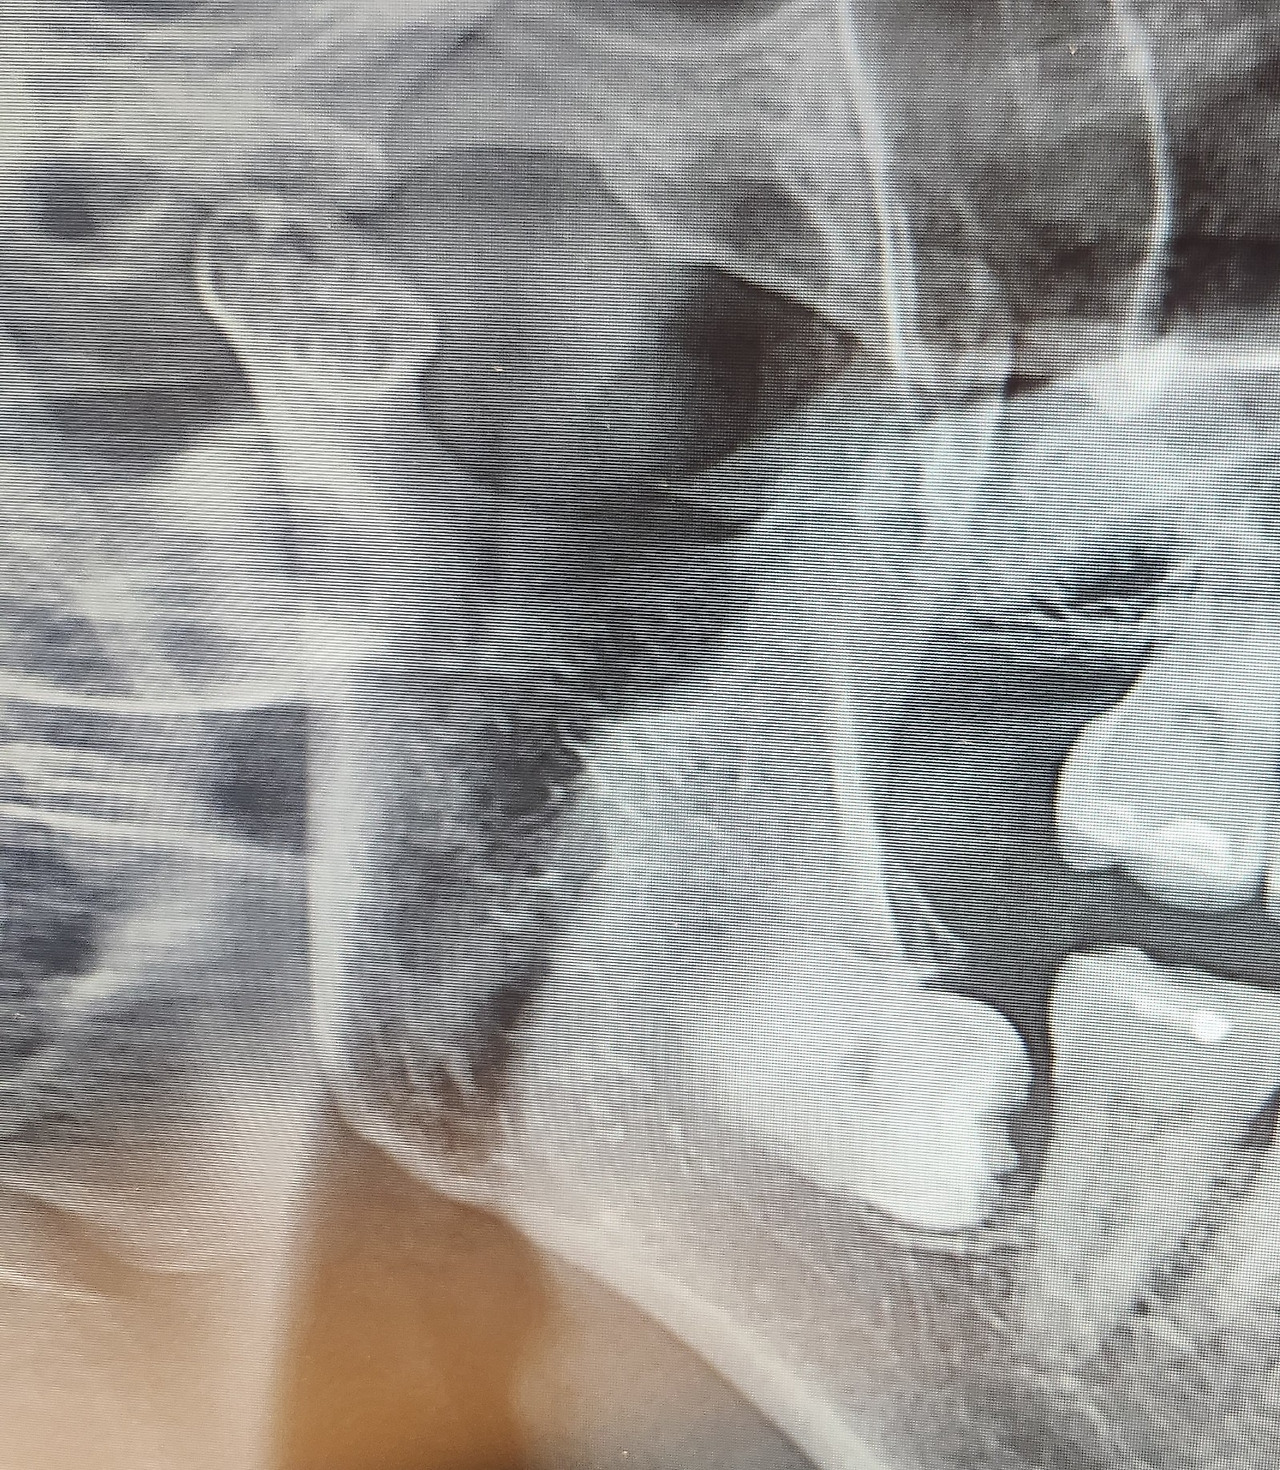

사랑니를 왜 여태 안 뽑았냐면 크게 불편하지 않아서였다. 그도 그럴 것이 사랑니가 겉으로 조금이라도 보였다면 이야기가 달라졌을 것이다. 내 사랑니는 잇몸 속에서 미라처럼 누워 오랜 세월을 보냈다. 내가 만약 치아 엑스레이라는 의료 장비가 없는 시대에 태어났다면 평생을 사랑니 존재를 모르고 살았을 것이다. 그러다 어느 날 지금처럼 시름시름 앓았을 것이고 그 뒤로 어떻게 됐을지 모를 일이다. 내가 내 잇몸 속 사랑니의 존재를 안 건 20여 년 전이었다. 위쪽 사랑니가 나오다 아프기 시작했다. 사진을 찍어보니 위쪽 사랑니는 잇몸 밖으로 빼꼼 모습을 드러낸 반면 아래쪽 사랑니 두 개는 잇몸 속에 파묻혀 있었다.

치과에서 이런 매복 사랑니는 결국 문제가 된다고 뽑아야 한다고 했다. 더군다나 일반 치과에서는 뽑지도 못하고 대학병원으로 가라고 했다. 하지만 굳이 아프지도 않은데 왜?라고 생각하며 오랜 세월을 보냈다. 그리고 이 나이에 아래쪽 사랑니에 문제가 생길 줄은 몰랐다. 죽을 때까지 잇몸 속에 파묻혀 나와 함께 생을 마감할 줄 알았던 사랑니가 자신의 존재를 확인시키고 있었다.

"사랑니가 신경과 너무 가깝게 있어서 신경을 건드리지 않고 뽑기는 힘들어요. 신경 손상이 예상됩니다. 20-30대는 회복이 되지만 나이가 있어서 영구 손상 가능성이 있어요. 너무 오래돼서 뼈와도 붙어 있어서 뼈도 깎아 내야 해요. 사랑니는 젊을 때 뽑았어야 해요."

나이는 내 신체를 지배하고 있다는 사실을 다시 한번 깨닫고 영구 손상이라는 두려운 단어에 질문들을 쏟아내기 시작했다. 질문의 대답은 매한가지였다. 여하튼 그대로 둘 수는 없으니 발치 예약을 했다. 그리고 치과를 나와 챗 GPT에게 내 사랑니 사진을 보여주며 신경 손상 정도를 예측해 달라고 했다. 챗 GPT는 생각 이상으로 치아 사진을 잘 분석했다. 그래도 영구적 신경 손상에 대해서는 의사 선생님이 말한 내용과 다르게 낮다는 소견을 내놨다. 어차피 빼야 하니 긍정 회로라도 돌리며 마음을 다잡아야 했다.